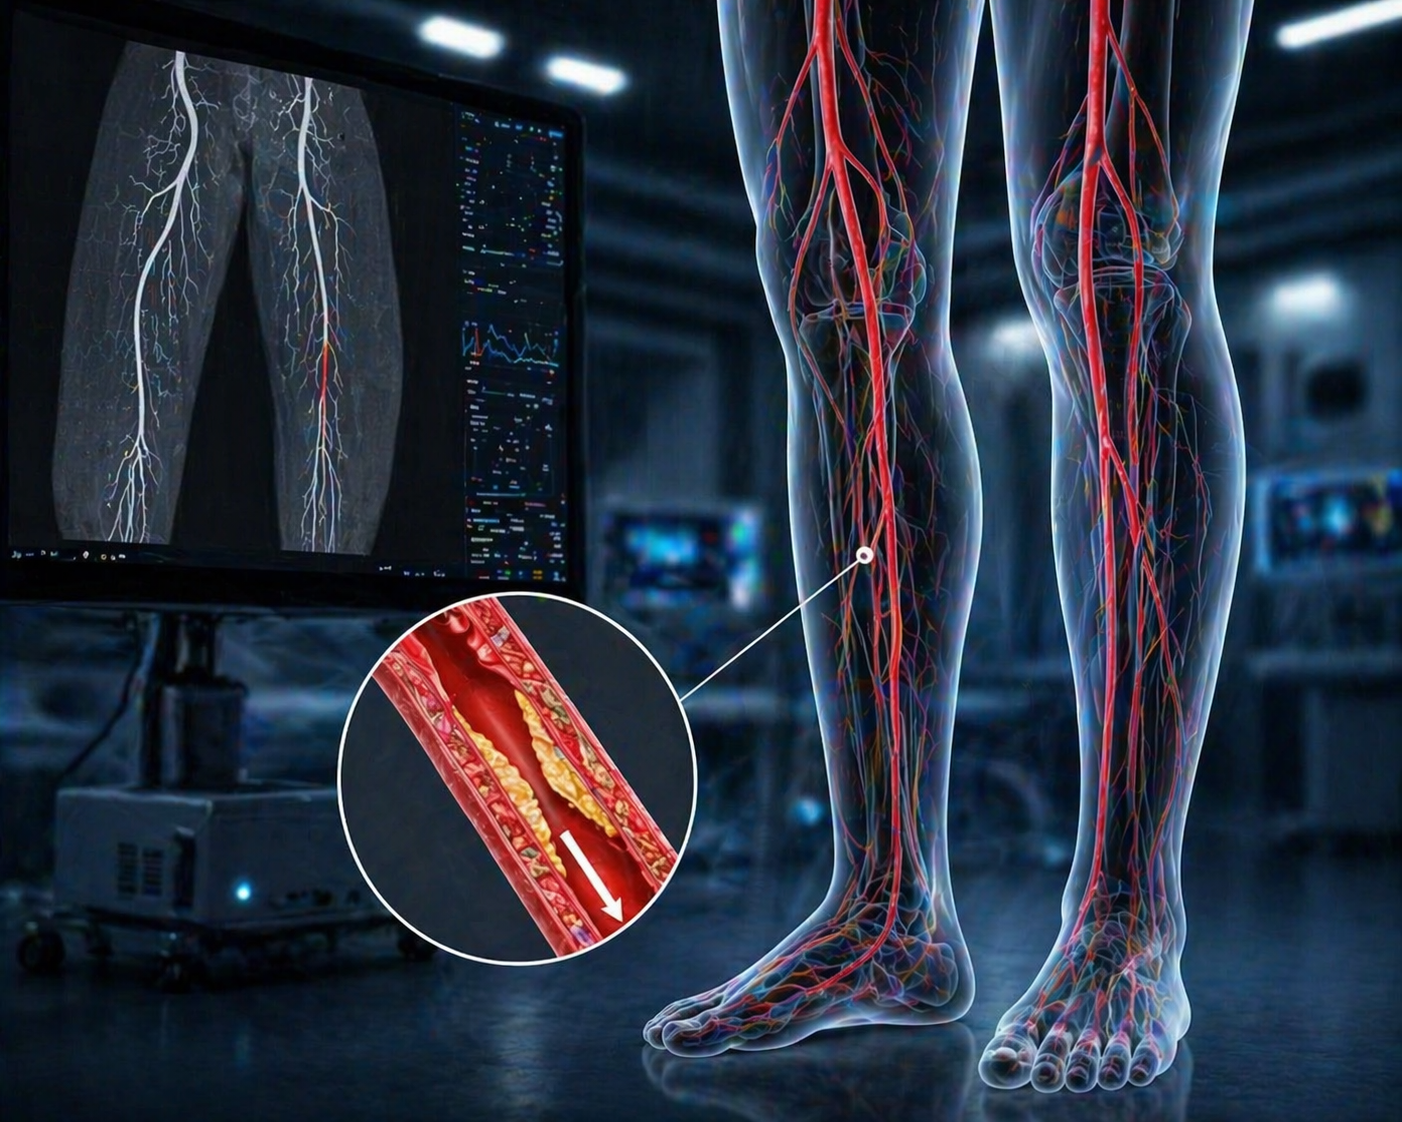

Targeted peripheral stenting to improve circulation with precision and monitoring for better outcomes.

Comprehensive care for peripheral arterial disease to improve circulation with expert monitoring and better outcomes.